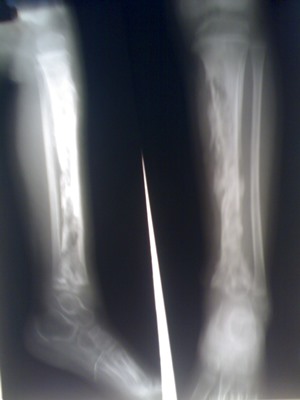

Для диагностики этого заболевания оценивается общая клиническая картина, а также проводится ряд лабораторных анализов. Также проводится рентген пораженного участка.